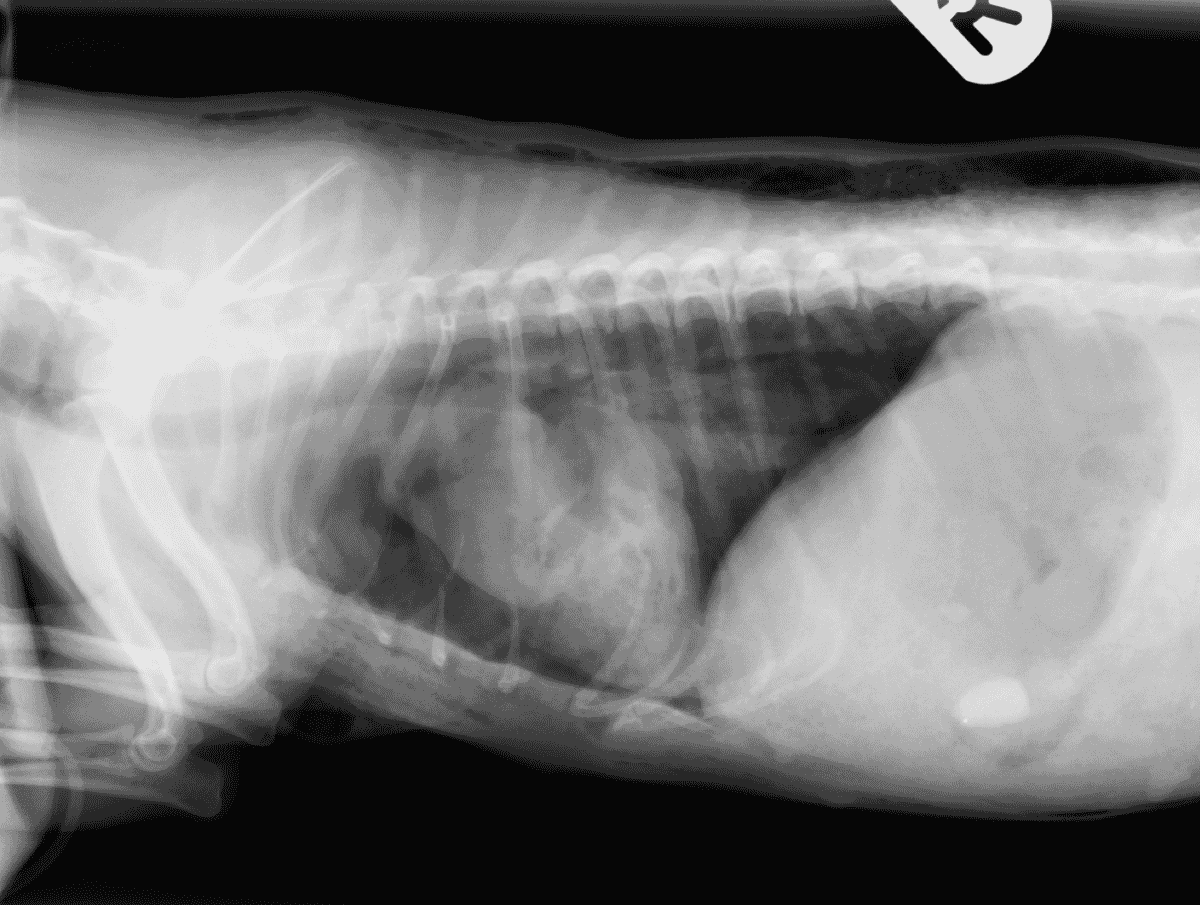

From www.veterinary-practice.com

Management of thoracic dog bite wounds Veterinary Practice Dog Bite Delayed Closure Dog bite wounds represent a major health problem. Infection rates were low (8.3%,. The aim of this review was to find out whether animal bite wounds heal better. Dog bites can have a primary closure at the time of injury. A study of 50 dog bite wounds revealed that the commonest colonizing: There is reasonable evidence that dog bite wounds. Dog Bite Delayed Closure.